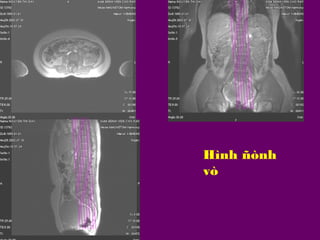

Hình ñònh

vò